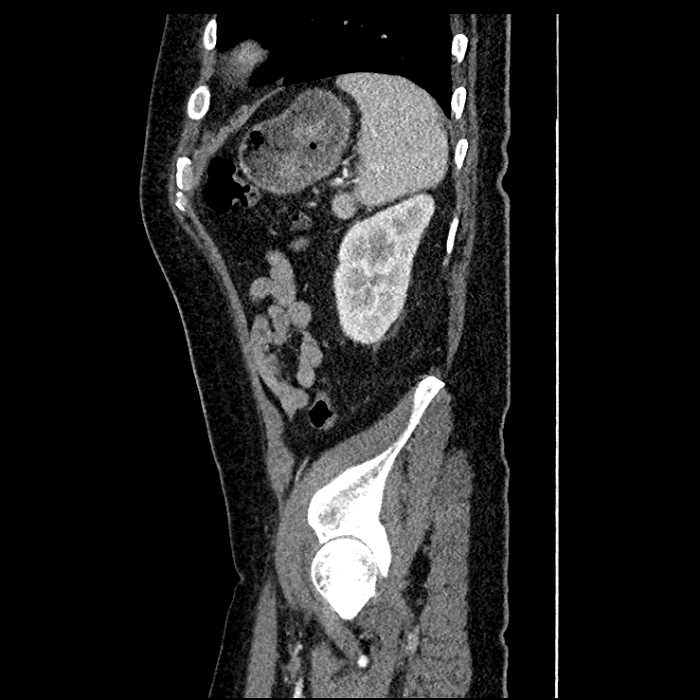

• Large fluid density structure in hepatic segments 7 and 8 measuring 10 x 7 x 7 cm with internal septation and circumferential ill-defined low density compatible with edema

• Clearly marginated fluid density structure in segment 7 and several other scattered tiny hypodensities, which likely represent cysts

• Hepatic abscess

Acute sigmoid diverticulitis complicated by a small contained perforation and a large abscess in the right hepatic lobe. Additional small subcapsular abscesses along the anterior margin of the left hepatic lobe.

• The classic CT imaging appearance is a double target sign with internal low density surrounded by an internal enhancing rim (capsule) and a low density external rim (edema)

Hepatic abscess showing the double target sign with low density internally surrounded by a thin inner enhancing rim (red arrow) and ill-defined outer low density rim (yellow arrow). Blue arrow indicates an internal septation. Red arrows: additional smaller subcapsular abscesses. Red arrow: focal contained perforation associated with diverticulitis.